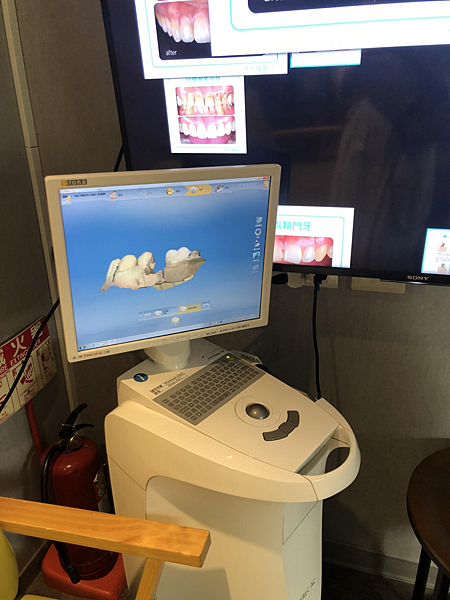

拥有3D导航植牙及口扫机与齿雕机的专业技术与仪器,引进德国的精密仪器聘请专业合格的技师进驻,一条龙的服务能避免植牙过程不必要的风险跟降低等待的时间~

确认完骨头跟回诊期间,悦庭会用3D的方式仿真我整个牙齿口腔的状况,非常精准的测量需要放置植体部位得深度及宽度,提高手术成功率,并降低风险。